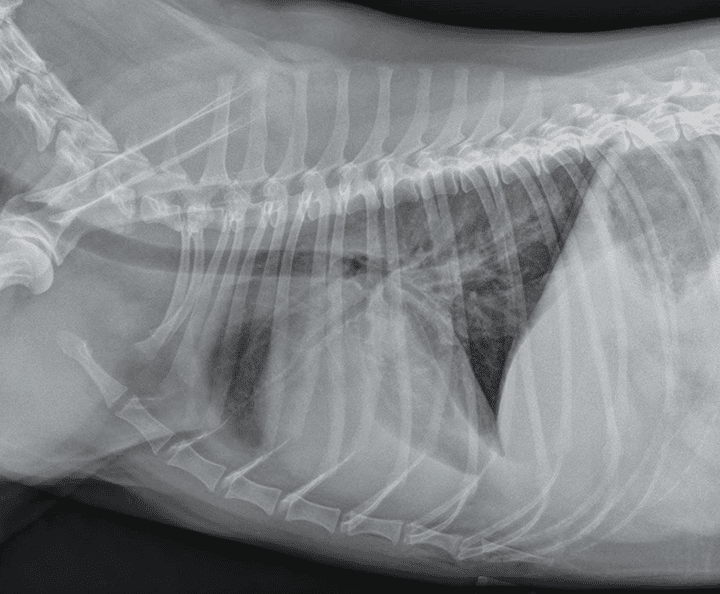

图1-图3是基于表3影像学征象的胸腔积液剖析。

图3犬右侧位胸片,患有继发于低蛋白血症的严重胸腔积液。心脏轮廓和横隔的边疆消逝,以及存在图1、图2中显现的胸腔积液的其他特征。图中有三个中央导管:中央静脉管(左下)、鼻饲管(中间), 和胸腔引流管(右上)。

动物胸腔积液时,肺叶间裂隙内会呈现软组织混浊或积液,其外围最宽,中央最薄。由于这些区域的积液,肋膈角和腰膈角会变钝。心脏轮廓和横隔的边疆将部分或完整消逝(图2)。在患有严重胸腔积液的患病动物中,气管可能向背侧升高(图 3)。